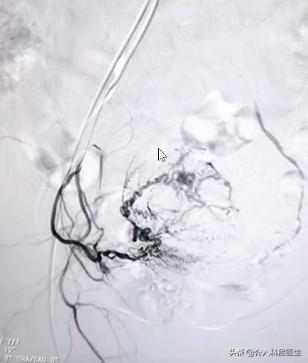

下图分别是左侧和右侧的子宫动脉,这些曲曲弯弯的血管,再栓塞后就消失了。两边的血管都必须要栓塞,这样才能让肌瘤坏死。但是只需要用一根针,整个手术伤口就是一个针眼,出血量就是和你打针输水时出的血差不多,非常的微创。